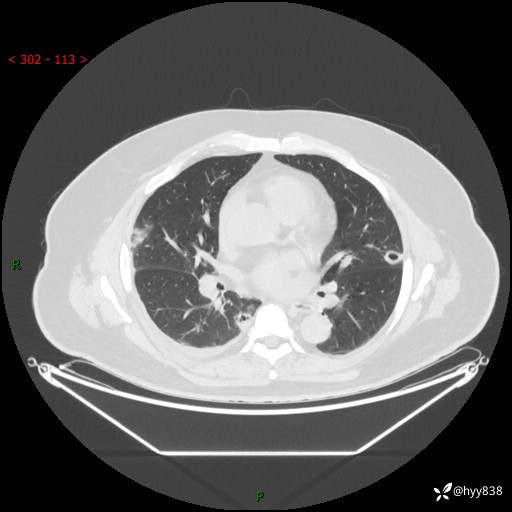

性别:男

年龄:48岁

简要病史:发热来诊(门诊病人)

胸部CT平扫